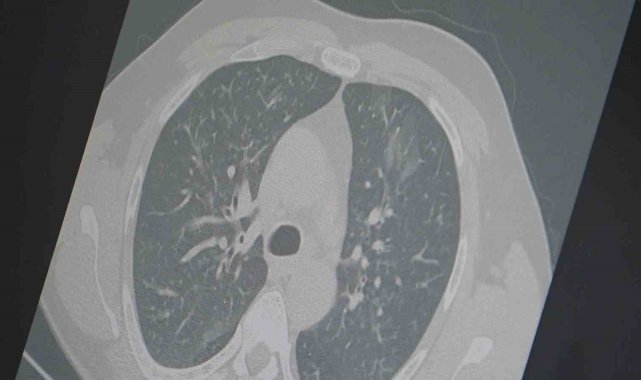

Son haftalarda ülke genelinde solunum yolu enfeksiyonlarında ciddi artış yaşandığın ifade eden Göğüs Hastalıkları Uzmanı Prof. Dr. Şevket Özkaya, aynı anda görülen influenza (grip), kovid-19 ve RSV virüslerinin toplumda "3'lü salgın" etkisi oluşturduğunu belirterek vatandaşları dikkatli olmaları konusunda uyardı.Prof. Dr. Özkaya, son dönemdeki hava şartlarına dikkat çekerek, "Sonbahar ve yaz karışımı bir iklimin etkisiyle gün içinde ani sıcaklık değişimleri yaşanıyor. Aynı gün içerisinde dört mevsimi birden yaşıyoruz. Bu durum bağışıklık sistemini zayıflatıyor ve grip benzeri şikayetlerle başlayan hastalık tabloları, üç farklı virüsün etkisiyle uzamış bir hal alıyor" dedi."Frankenstein varyantı Türkiye'de görüldü"Kovid-19'un "Frankenstein varyantı" olarak adlandırılan yeni türünün Türkiye'de de görüldüğünü ifade eden Prof. Dr. Özkaya, "Mevcut hastalarımız içinde kritik veya hayatı tehdit eden bir tablo yok. Ancak bu varyantın bulaşıcılığının yüksek olduğunu ve Avrupa ile Asya'da hızlı bir şekilde yayıldığını biliyoruz" diye konuştu."Zatürre riskine dikkat"Dr. Özkaya, grip ve kovid 19'un zatürreye dönüşme riski taşıdığını vurgulayarak, "Grip veya kovid sonrası birçok hastamızda hastalık akciğerlere iniyor ve zatürre olarak karşımıza çıkıyor. Hastaneye yatan hasta sayısında da artış gözlemliyoruz" şeklinde konuştu."Ayakta geçirilen ama bulaştırıcı bir salgın"Salgının günlük hayatı aksatmadan ancak sinsi bir şekilde yayıldığını belirten Özkaya, "Grip ve kovid artık yatağa düşürecek kadar ağır seyretmese de günlük işlerimizi yapmayı zorlaştırıyor. Ne tam hasta ne de tam iyilik hali olmadan virüs toplumda dolaşmaya devam ediyor. Dinlenmeyen ve izolasyon uygulamayan vakalar bulaş zincirini sürdürüyor" ifadelerini kullandı.Vatandaşlara uyarıProf. Dr. Özkaya, vatandaşlara şu önerilerde bulundu:"En ufak grip benzeri şikayeti olan vatandaşlarımızın evlerinde dinlenmelerini öneriyoruz. Uzamış öksürük ve nefes darlığı yaşayanların ise mutlaka doktora başvurarak akciğer röntgeni çektirmeleri ve uygun tedaviyi almaları gerekiyor."